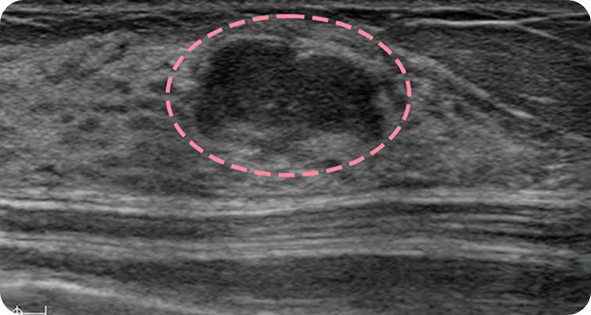

양성 종양은 여러 개가 동시에 생겨나기도 합니다. 정상적인 유방 조직 보전에 신경 쓰며 맘모톰 시술을 섬세히 진행했고, 6개월 뒤 추적 관찰을 위한 유방초음파에서 종양이 깨끗이 제거된 것을 확인 했습니다. 일부 반흔 조직은 자연스럽게 호전될 것으로 보여 좋은 예후가 기대되었습니다.